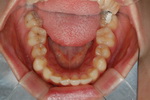

| ¾Õ´Ï ÃæÄ¡ |